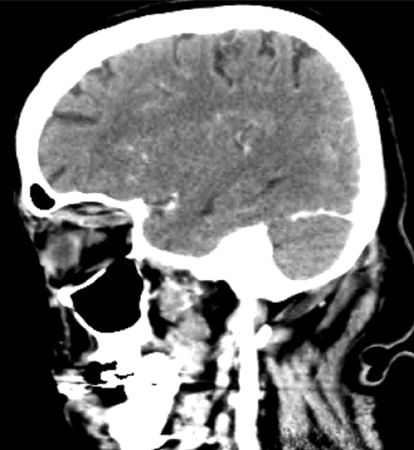

A TC e a RNM cranioencefálicas são as principais modalidades radiológicas usadas para confirmar o diagnóstico em todos os pacientes, e também são usadas para avaliar patologias causais e concomitantes.[43][52]​​​ Nenhuma das duas é absolutamente sensível ou específica para o diagnóstico de trombose do seio cavernoso (TSC). Uma TC com contraste é considerada superior à RNM para a detecção da formação inicial de coágulos nos seios cavernosos, enquanto a RNM é superior para o restante dos seios venosos durais.[55]​​

A TC é realizada idealmente pelo uso de uma técnica de escaneamento dinâmico com uma injeção em bolus e infusão contínua de contraste e uma varredura a intervalos seccionais próximos (menos de 3 mm) e em secções coronais e axiais.[63]

Extensões angiográficas da TC também podem ser realizadas.[Figure caption and citation for the preceding image starts]: Tomografia computadorizada (TC) sagital de crânio revelando uma veia oftálmica superior direita tubular aumentadaJones RG, Arnold B. Sudden onset proptosis secondary to cavernous sinus thrombosis from underlying mandibular dental infection. BMJ Case Rep. 2009;2009. pii: bcr03.2009.1671. Usado com permissão [Citation ends].com.bmj.content.model.Caption@5f487de6[Figure caption and citation for the preceding image starts]: Tomografia computadorizada (TC) de crânio na fase pós-contraste venosa (visão axial) revelando uma veia oftálmica superior direita aumentada em forma de "S" associada a proptoseJones RG, Arnold B. Sudden onset proptosis secondary to cavernous sinus thrombosis from underlying mandibular dental infection. BMJ Case Rep. 2009;2009. pii: bcr03.2009.1671. Usado com permissão [Citation ends].com.bmj.content.model.Caption@1799986a A venografia por TC também pode ser útil para confirmar o diagnóstico nos pacientes com suspeita de TSC.[52][53][54]​​